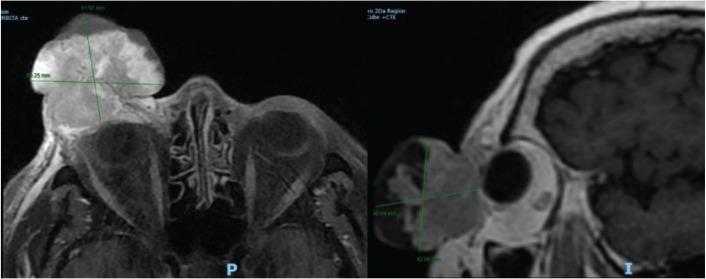

Merkel cell carcinoma (MCC) is a rare and aggressive tumour of the skin, characterised by a high rate of local recurrence and lymph node involvement. We present the case of a 58-year-old woman who developed a 5-cm tumour on the right lower eyelid, leading to ocular occlusion. Magnetic resonance imaging revealed an exophytic lesion in the right orbit, and a biopsy confirmed the diagnosis of MCC. After complete surgical resection and cervical emptying, the patient was treated with adjuvant radiotherapy. The final diagnosis was MCC, stage pT3 pN1 M0. The periocular location and tumour size were determinants in the treatment decision.